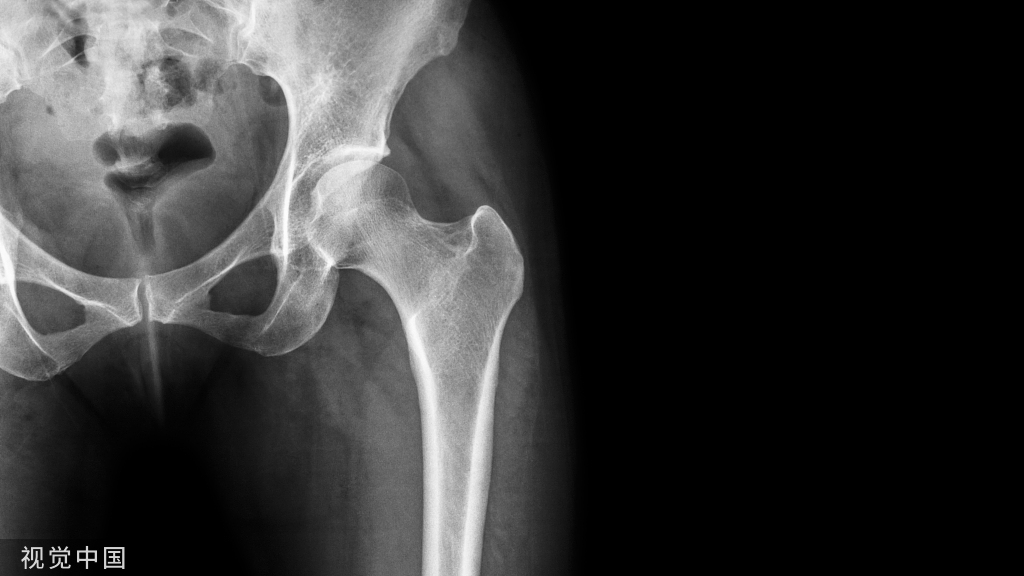

根据病情不同,术前检查有所不同,力求明确诊断。如果考虑髋关节撞击综合症,要做相应的特殊体位X片(骨盆正位+Dunn位),以及单髋盂唇核磁。不建议在当地医院检查,特殊体位检查需要有经验的医生和放射科医生合作才能完成,并且磁共振和CT这些检查档次也是不同的,在当地医院的检查只能作为参考。